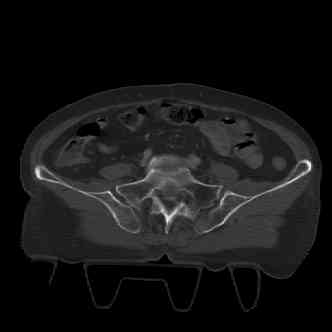

attached are images of a 70 year old female after peds versus car. her own car ran her over.

injuries are limited to the pelvis. left rami open and visible in a 10cm vertical laceration just lateral to left labia majora. wound is grossly clean. no vaginal and no urinary issues. CT scan shows widening of both SI joints anteriorly but I think this is vertically stable pattern.

attached are several CT cuts. please let me know if you need more. the CT is pre-pelvic ex-fix placement.